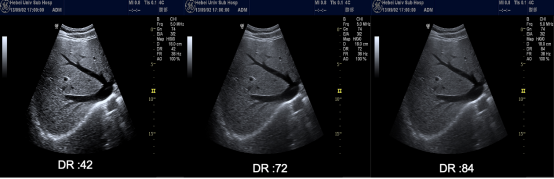

动态范围/动态对比(Dynamic Range/Dyn Cont)

! n1 ^2 ^% X1 q) d5 e 动态范围设置是用来调节图像灰度阴影对比度的重要参数。此设置可改变图像接收的最大和最小振幅比。低动态范围设置下的高对比度图像。有助于边缘图像质量的复杂研究。高动态范围图像则具有更多灰度层次。对于心脏取样来说,动态范围应提供足够的灰度层次,能更好地识别致密心肌和非致密心肌的界面。灰度层次过少会导致细节的忽略或缺失,例如:薄壁分隔,血栓,赘生物,当灰色阴影过多可能使图像“褪色”,使致密心肌和非致密心肌难以区别。